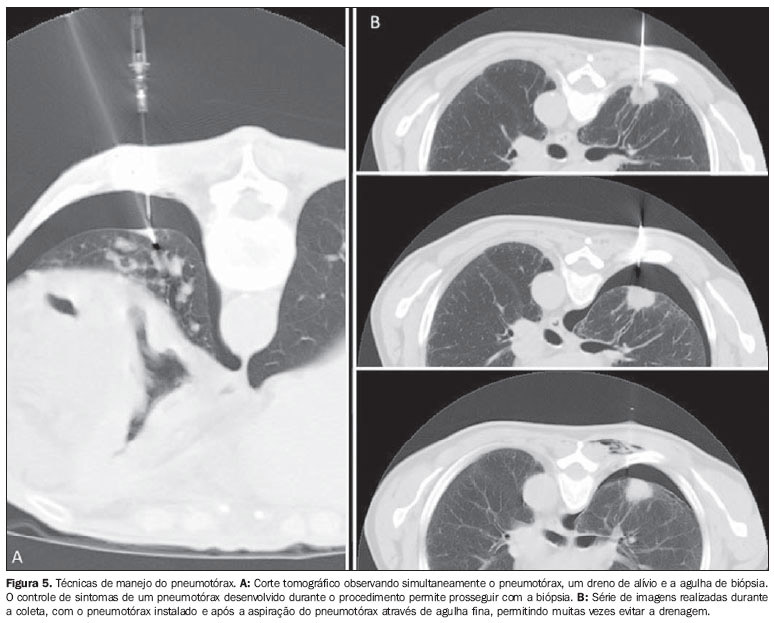

- Pneumotórax (ver pneumatórax): para tirar a amostra desejada, a agulha tem que perfurar o pulmão. Isso faz um pequeno buraco no órgão e o ar pode vazar no espaço ao redor. O furo geralmente é selado naturalmente, mas, se o vazamento de ar for muito grande, pode ocasionar um pneumotórax. Um pneumotórax pequeno, em geral, desaparece por conta própria, mas será preciso que seu médico acompanhe a situação. No caso de um colapso grande, o médico precisará colocar um tubo através do tórax para remover o ar que está vazando.